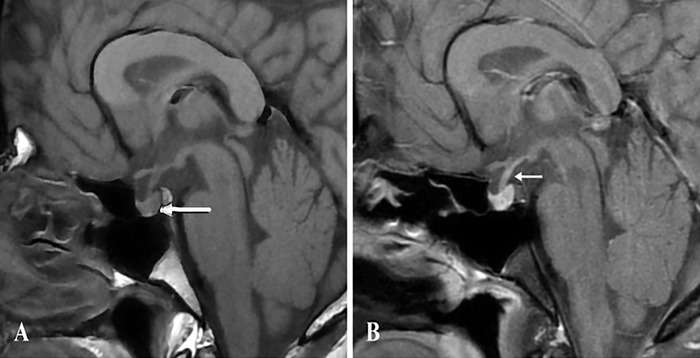

Case report: A 32-year-old male presented with polyuria (24-hour urine output of 144 mL/kg), polydipsia (24-hour fluid intake of 130 mL/kg), and nocturia of 6 months' duration. Baseline investigations revealed normal liver, renal, serum potassium, and blood glucose levels. After overnight dehydration, serum osmolality increased to 317 mOsm/kg, while urine osmolality remained inappropriately low at 156 mOsm/kg. Mild hypercalcemia (serum calcium of 11.1 mg/dL) was noted. Upon arginine vasopressin challenge, urine osmolality increased by nearly 300%, suggesting complete arginine vasopressin deficiency. Evaluation for secondary causes was unremarkable. Magnetic resonance imaging of the pituitary revealed a normal anterior pituitary and pituitary stalk with an absent posterior pituitary bright spot. Idiopathic arginine vasopressin deficiency was diagnosed. The patient responded to oral desmopressin replacement, and normocalcemia was documented in multiple samples repeated when the patient was in a hydrated state.